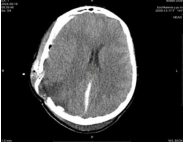

Figure 4: MSCT of the brain from 09/16/2024. Condition after surgery. Displacement of midline structures to the left (not distinct, weakly expressed positive dynamics). MSCT signs of subarachnoid hemorrhage. Additional hyperdense component in the cranial cavity in the frontal-parietal region on the right (subarachnoid hemorrhage? subdural hemorrhage?). MSCT signs of cerebral edema. MSCT picture of prolapse of the caudal contour of the cerebellar tonsils under the foramen magnum.

In the series of MSCT images Fig. 3, Fig. 4, Fig. 5, a shift of the midline structures of the brain to the left is visible, in Fig. 6, no shift of the midline structures of the brain is noted.